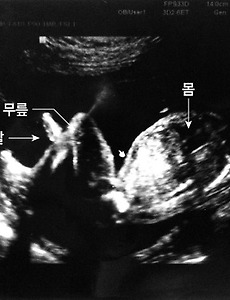

전체 글378 너 만의 명작을 그려라(마이클 린버그 저) 20대 때는 세상을 정의(定義)하는 것에 관심이 갔던 거 같습니다. 그때는 나 자신이 많이 혼란스러웠겠죠. (그때는 몰랐겠지만) 세상과 삶은 어떤 정의(定義)로 돌아가는지 배우고 싶어 읽었던 책인거 같습니다. 요즘을 두고 '철학의 부재의 시대'라고들 합니다. 이 책은 많은 위인들이 남긴 세상과 삶의 정의(定義)을 담고 있습니다. 책의 내용 중 슈바이처 박사의 글을 담아봅니다. 슈바이처는, “진리가 승리한다고 확신했던 사람이 지금은 더 이상 그런 확신을 가지고 있지 않다. 그는 인간을 믿었다. 그러나 지금은 아니다. 그는 선을 믿었다. 그러나 지금은 아니다. 그는 정의를 간절히 추구했다. 그러나 지금은 아니다. 그는 친절과 평화의 힘을 믿었다. 그러나 지금은 아니다. 그는 열정적인 사람이 될 수 있었다. .. 2011. 12. 16. 입체 초음파 사진을 찍었어요. (25주차 : 오늘 처음 긴장했습니다.^^;)[태아일기] 우리 아기의 초음파 사진입니다. 얼굴의 옆모습이죠. 지금 다니는 산부인과는 항상 입체 초음파 사진을 찍어주는 곳인데요. 처음 다니던 산부인과에 문제가 생겨 지금 다니는 산부인과로 옮겼는데요. 처음엔 산부인과를 옮기는 것에 집사람이 걱정 많이 했는데, 다행히 별 문제는 없더라고요. 옮기기를 잘 했단 생각도 들고요. 담당 선생님이 친절함과 확신의 믿음을 주시더라고요. 25주차인 이날은 병원 가면서 처음으로 긴장한 날이었습니다. 왜냐고요? 선생님께서 초음파 검사를 하는데 아기 손가락, 발가락 수 확인이랑 장기나 골격 등에 대한 상태를 말씀하시는 거예요. 다행히도 아무런 이상도 없어 다행이었는데, 처음 말씀하실 땐, 어! 이거 뭐지? 하면서 당황되고 긴장되더라고요. 혹시나 아기에게 잘못 있을까봐요. 그 때는 선.. 2011. 12. 16. 오~~~ 뭔가 형태가 나타나고 있습니다.(20주차 : 임신 기간의 중간 지점^^)[태아일기] 아래에 보이는 초음파 사진은 20주차 때 찍은 사진입니다. 20주차가 임신 기간의 중간 지점이라고 하더군요. 언제 키워서 언제 출산하나 했는데 벌써 반이나 지났네요. 이러다가 어~어~ 하다 출산하겠죠? 울 아기 빨리 보고 싶습니다. 그나저나 울 아이가 점점 사람같이 돼가고 있어요. 당연한 걸 알면서도 신기합니다. 그런데 사진에 얼굴이 안보이네요? 귀한 얼굴이니 자꾸 숨기나 봐요. 의사선생님의 말씀으론 외부자극으로부터 보호하기 위한 본능이랍니다. 점점 태동이 많아지나봐요. 집사람이 아이가 움직인다고 하면서 배를 만져보라고 하는데, 움직임이 미약해서 그런지 아직은 못 느끼겠더라고요. 그리고 우리 아기는 클래식을 좋아하나봐요. 집사람이 클래식을 들으면 마구 움직인다고 하네요. (대략 20주 이후부터는 외부의 .. 2011. 12. 16. Tools-4 [일러스트레이터,Illustrator] 오늘 알아 볼 툴들입니다. 1. Mesh Tool Mesh Tool은 오브젝트의 면을 그물망과 같이 만들어 줍니다. ② Mesh Tool을 선택해 사각형의 면을 클릭해 그물망 포인트를 만들어 줍니다. ③ 그물망 포인트를 이동하고 포인트의 컬러를 조정합니다. ④ 결과물입니다. 입체감이 생겼죠? (아니라고요? 제가 잘 못 해서 그래요.^^;) 2. Gradient Tool ① 그라데이션이 있는 박스입니다. ② 그라데이션 박스를 선택하면 그라데이션을 조정할 수 있는 바가 생깁니다. 그림은 조절바에 마우스 커서를 올린 모습입니다. ③ 조절바를 이용해 그라데이션의 컬러와 위치를 조정했습니다. 3. Eyedropper Tool 보통 스포이드 툴이라고도 하는데, 오브젝트A에 오브젝트B와 같은 성격을 부여할 때 쓰입니.. 2011. 12. 15. Tools-3 [일러스트레이터,Illustrator] 이번 페이지에서 알아볼 툴들입니다.툴들을 설명해보니 그동안 설명 드렸던 메뉴에 비해 설명이 수월하네요. 언어로 실행되는 명령어와 나의 손을 움직이는 모션적 툴의 차이점일까요? 아니면 툴의 아이콘을 직관적으로 잘 만들어서 일까요? 우리의 행동 양식을 이용해 만들어진 직관적 프로그램 툴은 다가가기 참 쉬운 거 같습니다. 1. Rotate Tool 오브젝트를 회전시킵니다. - Rotate Tool 아이콘을 더블클릭하면 아래와 같은 조절창이 열리고, 회전할 각도의 수치를 입력해 오브젝트를 회전시킬 수 있습니다. 2. Reflect Tool 오브젝트를 반전시킵니다. 3. Scale Tool 오브젝트를 확대·축소시킵니다. - Scale Tool 아이콘을 더블클릭하면 아래와 같은 조절창이 열립니다. 4. Shear .. 2011. 12. 14. 한권으로 읽는 드러커 100년의 철학(피터 드러커 저) 언제부턴가 책을 볼 때면 밑줄을 치곤합니다. 그리고 컴퓨터에 타자를 처 보관하곤 했습니다. 그 글들을 올려봅니다. 저작권으로 문제가 생기진 않겠지요? 괜찮은 책이니 밑줄처서 블로그에까지 올리겠죠? 구입해 읽어보세요~ (← 혹시 문제 생길까봐...ㅋㅋㅋ) 혹시 저작권에 문제가 있다면 메일 남겨주세요. 성공의 열쇠는 책임이다. 책임 있는 존재가 되는 것은 진지하게 일에 몰두하고, 자신이 성장해야 할 필요성을 인식하는 것이다. 중요한 임무를 맡게 되면 스스로를 중요하다고 느낀다. 자기개발이란 능력을 쌓는 것만이 아니라 인간으로서 상장해 나가는 것이다. 책임에 초점을 둠으로써 보다 큰 자신을 발견하게 된다. 성과를 올리는 사람과 그렇지 못하는 사람의 차이는 재능이 아니다. 몇 가지 습관적인 자세와 기초적인 방법.. 2011. 12. 12. 한국의 이공계는 글쓰기가 두렵다.(임재춘 저) 언제부턴가 책을 볼 때면 밑줄을 치곤합니다. 그리고 컴퓨터에 타자를 처 보관하곤 했습니다. 그 글들을 올려봅니다. 저작권으로 문제가 생기진 않겠지요? 괜찮은 책이니 밑줄처서 블로그에까지 올리겠죠? 구입해 읽어보세요~ (← 혹시 문제 생길까봐...ㅋㅋㅋ) 혹시 저작권에 문제가 있다면 메일 남겨주세요. 블로그를 쓰게 되면서 제게 생긴 변화가 두가지 있습니다. 그 전 같으면 “무심히 넘어갔을 것들에 대한 관심”과 “글 쓰는 법”입니다. 이 책은 어느 동생에게서 들어 알게 된 책인데, 제가 블로그를 쓰지 않았다면 만나지 못했을 책일 겁니다. ‘알고 있다’라는 말은 다시 한 번 되새겨 보자. 진정으로 알고 있다는 것은 다른 사람들에게 자신의 논리를 펴서 이해시킬 수 있고 설득할 수 있다는 것을 의미한다. 아마추어.. 2011. 12. 12. 프리젠테이션 잰(가르 레이놀즈 저) 언제부턴가 책을 볼 때면 밑줄을 치곤합니다. 그리고 컴퓨터에 타자를 처 보관하곤 했습니다. 그 글들을 올려봅니다. 저작권으로 문제가 생기진 않겠지요? 괜찮은 책이니 밑줄처서 블로그에까지 올리겠죠? 구입해 읽어보세요~ (← 혹시 문제 생길까봐...ㅋㅋㅋ) 혹시 저작권에 문제가 있다면 메일 남겨주세요. 컨퍼런스 강연의 보조 자료로서 ‘시각 자료’는 얼마나 사용되고 있는가? “말보다 기억에 오래 남는 것이 시각 자료다. 하지만 여전히 대부분 슬라이드에 글머리 기호가 가장 많이 쓰이며 시각 자료는 거의 사용하지 않는다. 같은 내용이 글과 음성으로 동시에 주어지면 정보 처리가 훨씬 어려워진다. 차라리 발표자가 입을 다물고 청중들이 화면상의 글을 스스로 읽게 하는 편이 더 나을지도 모른다. 준비 단계에서는 우선 마.. 2011. 12. 12. 슬랙(톰 드마르코 저) 언제부턴가 책을 볼 때면 밑줄을 치곤합니다. 그리고 컴퓨터에 타자를 처 보관하곤 했습니다. 그 글들을 올려봅니다. 저작권으로 문제가 생기진 않겠지요? 괜찮은 책이니 밑줄처서 블로그에까지 올리겠죠? 구독해 읽어보세요~ (← 혹시 문제 생길까봐...ㅋㅋㅋ) 혹시 저작권에 문제가 있다면 메일 남겨주세요. 건강한 지식 기업은 직원들을 오랫동안 보유하는 능력이 뛰어나다. 도메인 지식을 올바르게 이해하는 방법은 그러한 지식들을 마치 기업의 금융 자산처럼 생각하고 직원들에게 기업이 투자한 것으로 간주하는 것이다. 만약 여러분이 인적 자본의 가치에 대해 엄격한 회계 처리를 한다면, 한 사람이 조직을 떠날 때마다 엄청난 손실이 발생했다고 처리할 수 밖에 없을 것이다. 만약 시장이 이미 포화 상태에 있거나 또는 거의 포화.. 2011. 12. 12. 마켓 3.0(필립 코틀러 저) 언제부턴가 책을 볼 때면 밑줄을 치곤합니다. 그리고 컴퓨터에 타자를 처 보관하곤 했습니다. 그 글들을 올려봅니다. 저작권으로 문제가 생기진 않겠지요? 괜찮은 책이니 밑줄처서 블로그에까지 올리겠죠? 구독해 읽어보세요~ (← 혹시 문제 생길까봐...ㅋㅋㅋ) 혹시 저작권에 문제가 있다면 메일 남겨주세요. 마케팅? 경제학? 경영학? 저 이런거 잘 모릅니다. 하지만 관심은 많습니다. 재미있기도 하고요. 이 책 무척 재미있어요. 마케팅, 경제, 경영에 대한 책도 재미있을 수 있습니다.ㅋㅋㅋ 관심만 있다면요. IBM은 직원들에게 자신의 블로그를 만들어 특정한 지침을 거스르지 않는 한도 내에서 회사에 대한 의견을 자유롭게 교환하도록 장려하고 있다. GE의 경우 트윗 팀을 조직해 일단의 젊은 직원들로 하여금 나이 든 직.. 2011. 12. 12. the one page proposal(패트릭 G. 라일리 저) 언제부턴가 책을 볼 때면 밑줄을 치곤합니다. 그리고 컴퓨터에 타자를 처 보관하곤 했습니다. 그 글들을 올려봅니다. 저작권으로 문제가 생기진 않겠지요? 괜찮은 책이니 밑줄처서 블로그에까지 올리겠죠? 구독해 읽어보세요~ (← 혹시 문제 생길까봐...ㅋㅋㅋ) 혹시 저작권에 문제가 있다면 메일 남겨주세요 기획서 쓸 일도 없는 제가 왜 이런 책에 관심을 가졌었는지 오래전이라 기억에 없지만, 많은 것을 얻었던 책입니다. 꼭 읽어보시길 강력 추천합니다. 기획서의 형식은 제목, 부제, 목표, 2차 목표, 논리적 근거, 재정, 현재 상태, 실행 등의 8개 부문으로 나뉘다. 오히려 완벽한 사업 기획서는 서류를 읽기도 전에 그들을 좌절시키는데, 영어 실력이 뒷받침되지 않아서일 수도 있고 미국 스타일의 차트나 그래프. 기술적.. 2011. 12. 12. 집사람이 받은 생일 선물 집사람이 생일 선물을 받았습니다. 아직 1달은 남았는데 벌써 선물을 받았네요. 아는(저도 아는) 언니랑 간송미술관 갔다가 책 이야기를 했는데, 거기서 언니가 필(feel) 받아 선물하겠다고 했었다네요. 그 언니는 그냥 기분으로 말했다해도 실천으로 잘 옮기시는 분이거든요. 책을 네권이나 선물 받으니 부자가 된거 같아요. 선물 받은 책들입니다. 요즘 제가 읽는 책들과는 분위기가 다른, 차가운 머리가 아닌 따듯한 가슴으로 읽는 책들이네요. 1. 무량수전 배흘림기둥에 기대서서 : 언니가 추천했다는 책입니다. 꼭 봐야겠어요. 2. 간송 전형필 : 간송미술관을 만드신 분의 책이라네요. 3. 어린 왕자 : 이 책으로 차가워지고 있는 가슴을 덥여봐야겠습니다. 4. 윤미네 집(윤미 태어나서 시집가던 날까지) : 아빠가 .. 2011. 11. 25. 무자각한 악의 "무자각한 수동적 생각과 행동이 악의를 만든다"는 비판을 담은 대화입니다. (애니메이션 "건담 더블오" 중에서) 2011. 11. 9. 디자인 하지 않는 디자이너(나가오카 겐메이) 언제부턴가 책을 볼 때면 밑줄을 치곤합니다. 그리고 컴퓨터에 타자를 처 보관하곤 했습니다. 그 글들을 올려봅니다. 저작권으로 문제가 생기진 않겠지요? 괜찮은 책이니 밑줄처서 블로그에까지 올리겠죠? 구독해 읽어보세요~ 브랜드라는 것은 당연한 말이지만 마크만을 의미하지는 않는다. 그리고 또한 브랜드라는 것은 ‘브랜드를 만든다.’ 는 의식이 없으면 절대로 만들어지지 않는다. 적어도 나는 그렇게 생각한다. ‘브랜드를 만든다.’는 것은 세상에서 흔히 쓰는 느낌으로 ‘하나의 브랜드를 목표로 하여 만드는 행위’는 아니다. ‘내가 하고 있는 일이 바로 브랜드’라고 의식하며 그것을 철저하게 만드는 의식. 분명 그런 의식을 가지고 수년, 수십 년 동안 그것을 반접하는 것을 손님이 인정했을 때, 축하할 만한 브랜드가 되는 .. 2011. 11. 7. 게으름에 대한 찬양(버트런드 러셀) 언제부턴가 책을 볼 때면 밑줄을 치곤합니다. 그리고 컴퓨터에 타자를 처 보관하곤 했습니다. 그 글들을 올려봅니다. 저작권으로 문제가 생기진 않겠지요? 괜찮은 책이니 밑줄처서 블로그에까지 올리겠죠? 구독해 읽어보세요~ 일이란 무엇인가? 일에는 두 가지가 있다. 먼저 지표면 혹은 지표면 가까이 놓인 물질을 다른 물질과 자리를 바꿔 놓는 일이다. 또 하나는 타인들에게 그런 일을 하도록 시키는 일이다. 4시간 노동으로 생활필수품과 기초 편의재를 확보하는 한편, 남는 시간은 스스로 알아서 적절한 곳에 사용하도록 되어져야 한다는 뜻이다. 현명하게 더 많은 교육이 이루어지고 그 교육의 목표에 여가를 현명하게 사용하는 데 필요한 안목을 제공하는 항목이 들어 있어야 한다는 것은 어느 사회에서나 필수적이다. 도시 사람들의.. 2011. 11. 5. 물통의 법칙 (혼자만 잘 살믄 무슨 재민겨) 물통의 법칙이란 게 있어요. 옛날에는 요사이 시장에서 파는 명란통 같은 물통을 나무로 만들었습니다. 판자를 여러 쪽 모아 통을 짜는데 높고 낮은 판자로 통을 짰다고 합시다. 물은 가장 낮은 판자 높이밖에 차지 않아요. 지금 농민들은 농사짓는 일은 아주 열심히 합니다. 겨울에 하우스까지 만들어 죽자 살자 일해요. 그래서 한쪽 판자는 굉장히 높아요. 한편 스스로와 세상을 만드는 일에는 무관심해서 다른 쪽 판자는 아주 낮아요. 새빠지게 물을 부어 봤자 물은 낮은 판자까지만 차지 절대로 더 높이 올라가지 않지요. 그 차가 심할수록 좌절감은 크고 한은 사무칩니다. 전우익 님의 중에서 앞만 보고 달리는 거 좋습니다. 하지만, 가끔 주변도 봐주세요. 그러면 주변의 새로운 것에 즐거움을 느끼기도하고, 내 주변의 모르던.. 2011. 11. 2. Tools-2 [일러스트레이터,Illustrator] 이번 페이지에서 알아볼 툴들입니다. 팝업창에 가려졌던 툴까지 같이 보니 꽤 많네요. 1. Pen Tool 선을 그릴 때 쓰입니다. 선의 시작점과 끝점이 만나면 닫힌 선이 됩니다. 2. Add Anchor Point Tool 오브젝트에 점을 추가 시켜줍니다. 3. Delete Anchor Point Tool 오브젝트에 점을 삭제 시켜줍니다. 4. Convert Anchor Point Tool 중간에 위치하는 점을 수정할 수 있습니다. 5. Type Tool 글자를 입력할 수 있습니다. 6. Area Type Tool 임의의 오브젝트 안에 글자를 입력할 수 있습니다. 7. Type on a Path Tool 선을 따라 흐르는 글자 만들 수 있습니다. 8. Vertical Type Tool 글자 세로로 쓸 수.. 2011. 10. 31. Tools-1 [일러스트레이터,Illustrator] 드디어 힘들었던 ‘메뉴의 명령어’ 설명이 끝나고 툴 설명으로 넘어왔습니다. 오늘부터 몇 페이지는 Tool에 대한 설명입니다. Tool은 도구란 뜻이죠? Adobe Illustrator CS5는 무척 다양한 도구를 준비하고 있습니다. 위의 그림을 보니 무척 다양한 도구들이 있죠? 각각의 도구들은 용도를 직관적으로 알수 있게 아이콘으로 돼있습니다. 위부분의 Tool부터 설명하겠습니다. 그전에 Tool bar의 형태에 대해 잠깐 알아볼게요. 1. Selection Tool 클릭 또는 드레그해서 오브젝트를 선택할 수 있습니다. 보통 선택할 때는 이 툴을 많이 사용합니다.선택하면 오브젝트가 위와 같은 모습을 보입니다. 2. Direct Selection Tool 오브젝트의 일부분인 점이나 선을 선택할 때 주로 쓰.. 2011. 10. 29. 이전 1 ··· 15 16 17 18 19 20 21 다음 반응형